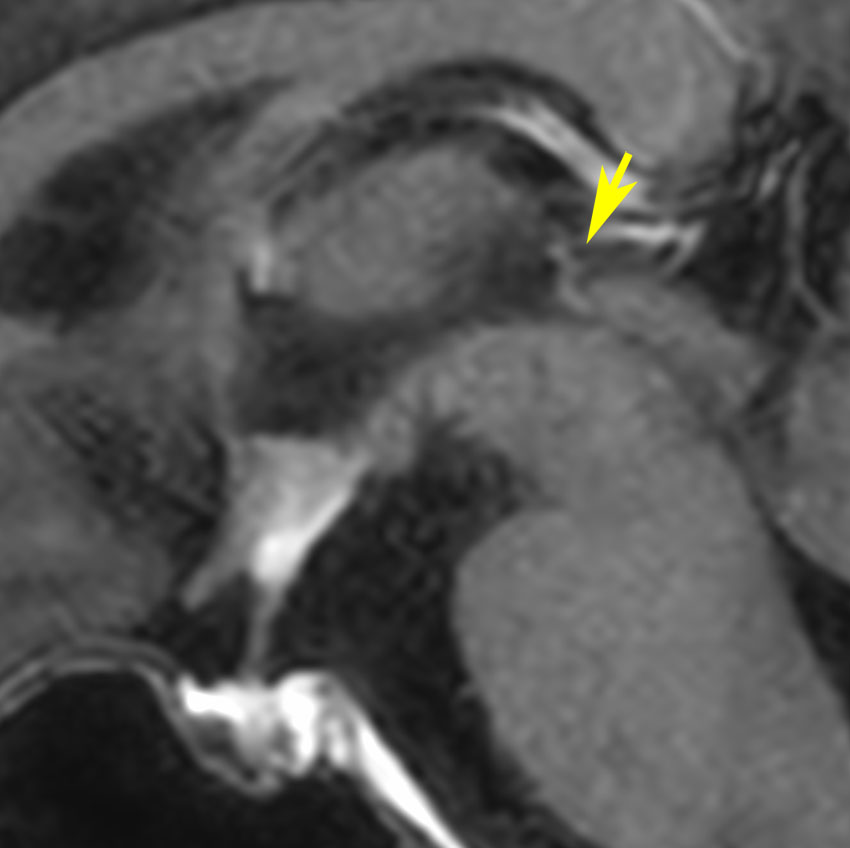

放射線が外れやすい部位は再発源となります

側脳室先端(前角,後角,側頭角,閂),下垂体と大脳基底核に放射線が入らないとその部位から再発します。

再発ジャーミノーマの画像です。延髄背側の閂 ovexという部位に再発しています。

このパターンはとても多いです。なぜかというと,全脳室照射の時に,第4脳室下端のovexの上衣 ependyum を照射野に入れない放射線治療医の先生がいるからです。放射線科の先生にもちょっとした知識が必要なのです。

これは再治療で腫瘍が消えても不可逆的な重症の延髄障害を残してしまいます。